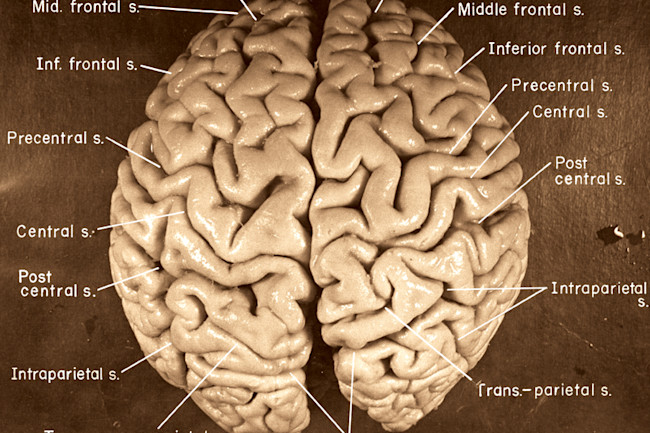

As we saw earlier, the human brain is about three times as big as expected in a primate of our size. Listen free to The Pillows – NOOK IN THE BRAIN (Envy, 王様になれ and more). I hope you all stay healthy and safe.